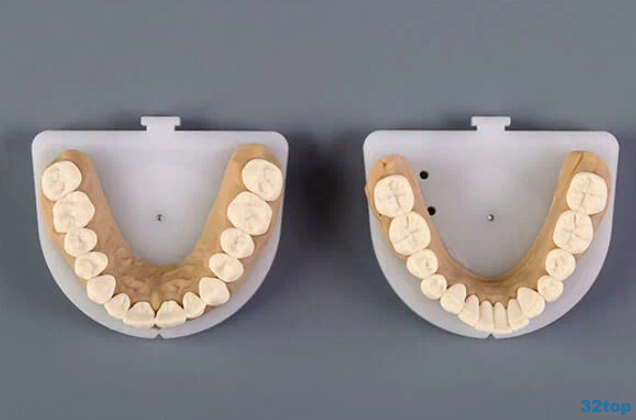

Циркониевая коронка за 34000 рублей.

Циркониевая коронка под ключ со скидкой 20% за 34000 рублей.